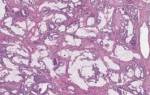

Карциноид легкого — группа легочных новообразований нейроэндокринной природы, имеющих злокачественный характер. При этом карциноидные опухоли чаще всего длительно протекают бессимптомно и обнаруживаются случайно.

Карциноид легкого может быть двух типов — типичный и атипичный.

- Типичные карциноидные опухоли легких представляют собой наиболее хорошо дифференцированный и наименее биологически агрессивный тип легочных злокачественных новообразований. Эти опухоли характеризуются медленным ростом и редко имеют тенденцию к метастазированию.

- Атипичный карциноид — более агрессивная опухоль как с точки зрения морфологии (более инвазивный рост), так и с точки зрения клинической картины. Эти опухоли характеризуются быстрым ростом и относительно ранним началом метастазирования.

Долгое время карциноид легкого вследствие особенностей морфологии и течения его типичных форм принято было относить к доброкачественным опухолям с возможностью малигнизации (озлокачествления). Однако современные исследования убедительно доказали ошибочность этого подхода. И сегодня европейская онкология однозначно относит все формы карциноида легкого к злокачественным опухолям.